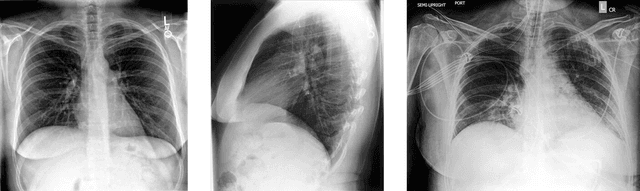

Recent advances in deep learning have led to a promising performance in many medical image analysis tasks. As the most commonly performed radiological exam, chest radiographs are a particularly important modality for which a variety of applications have been researched. The release of multiple, large, publicly available chest X-ray datasets in recent years has encouraged research interest and boosted the number of publications. In this paper, we review all studies using deep learning on chest radiographs, categorizing works by task: image-level prediction (classification and regression), segmentation, localization, image generation and domain adaptation. Commercially available applications are detailed, and a comprehensive discussion of the current state of the art and potential future directions are provided.